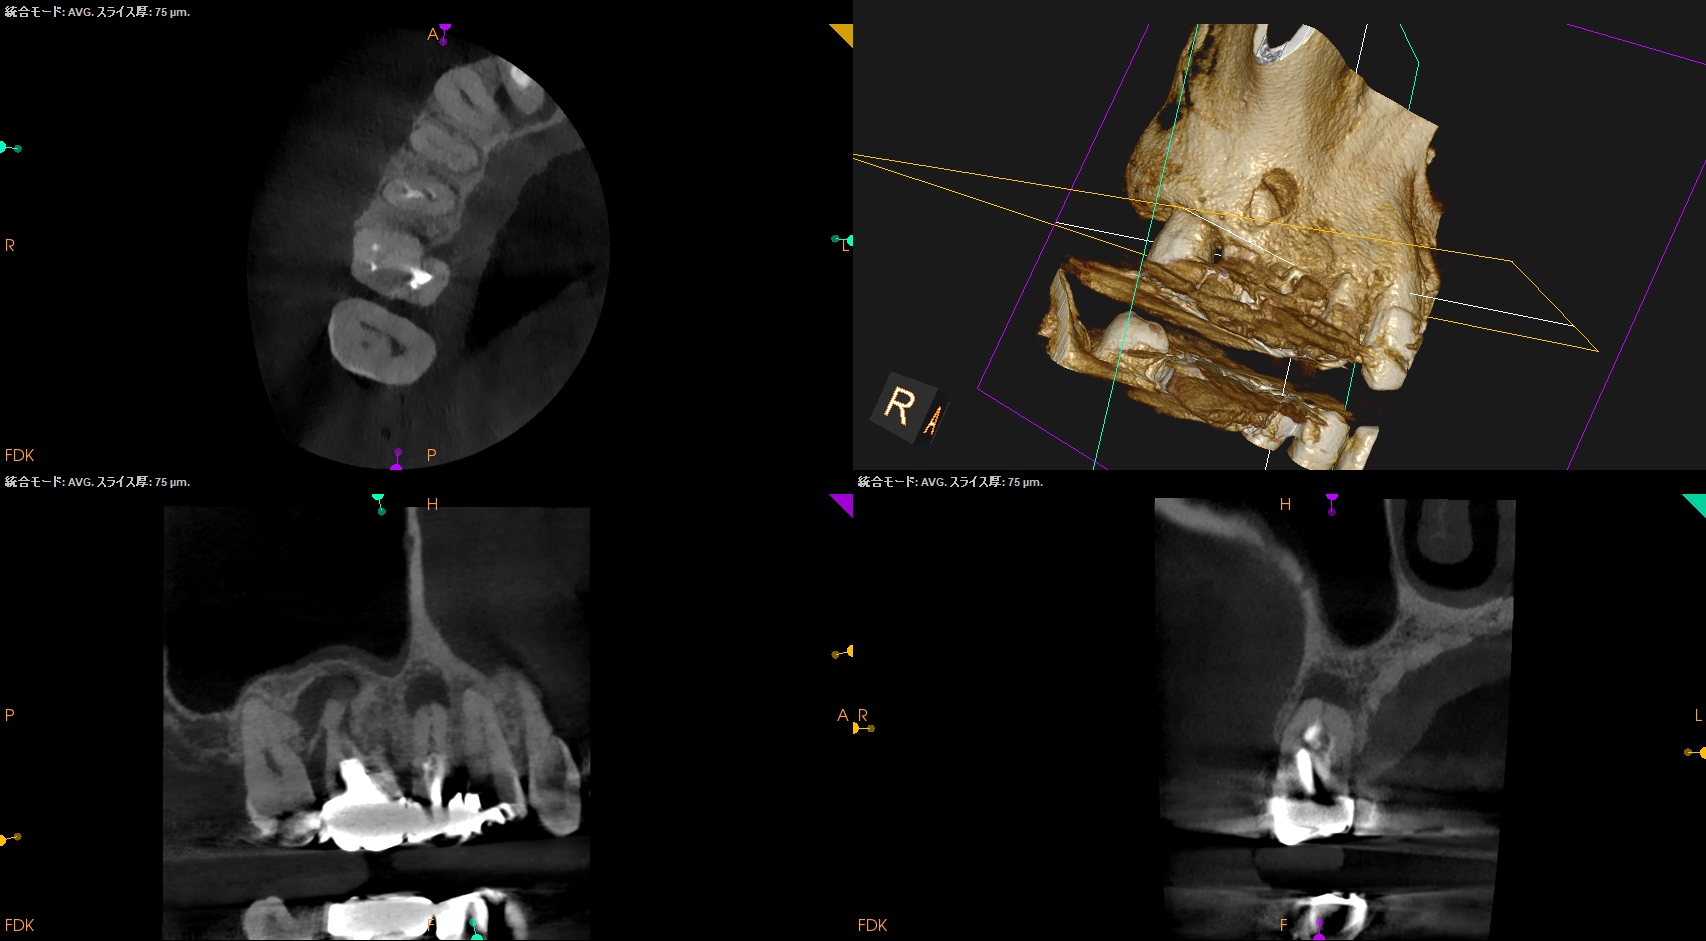

CBCT(2025.9.22)

#4

#3 MB

DB

P

これで抜歯とは…意味がわからない。